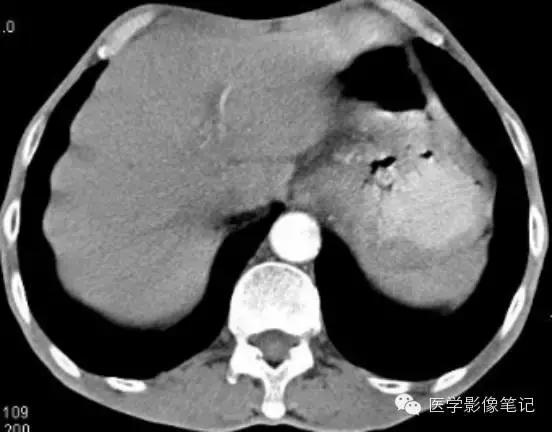

肝左叶缺如

右叶发育不全

内脏反转